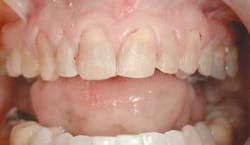

With our patient, this evaluation reveals the centrals to be approximately 8.5 mm wide and 9.5 mm long. (Fig. 3) This would make the existing W/L ratio 89 percent. The Golden Proportion evaluation shows that the centrals appear too wide and we see too much of the canines.

In fig. 5, we can see how our patient presents before we begin our treatment. Using the guidelines above, we can now see what corrections we need to make.